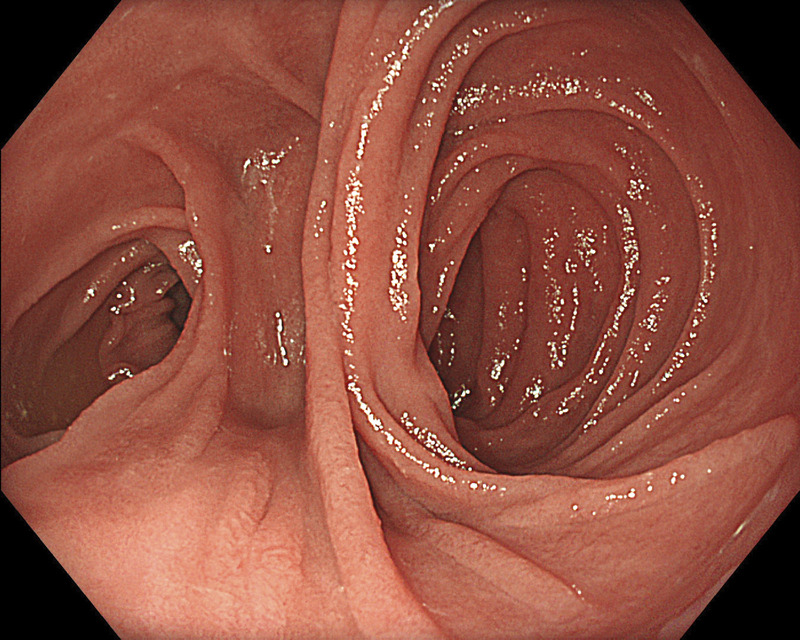

Abstract Image